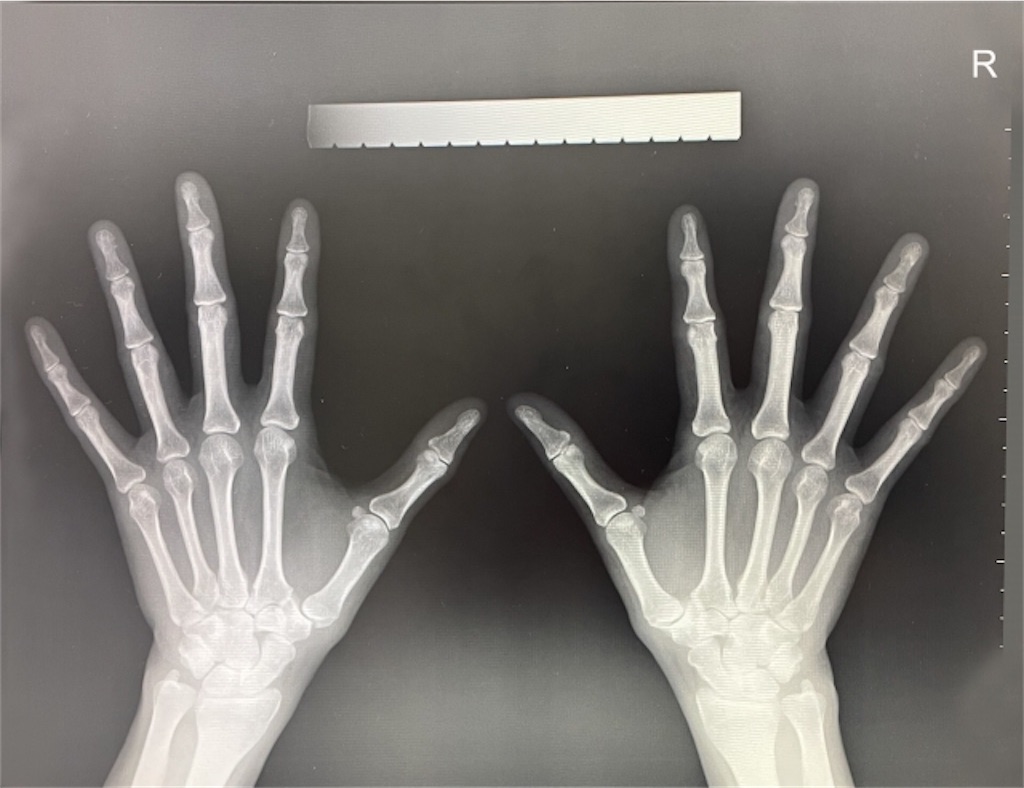

その後レントゲン。

医師は懇切丁寧に説明してくれた…と思うが、実はあまり記憶にない。

はっきり覚えているのは

👨⚕️「年齢を考えれば特別気にしなくてもいい」

大事なことなのでもう一度書く。